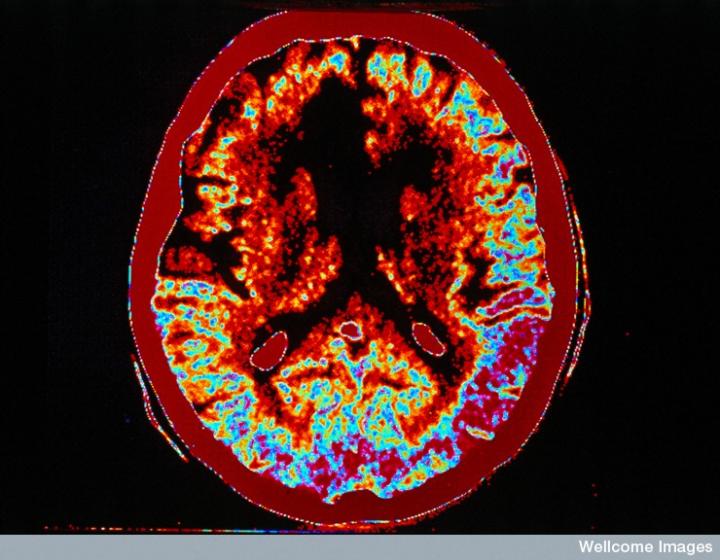

CT掃描的主圖顯示左側有一些中風損傷,由 Wellcome Images提供。Wellcome Photo Library提供的慢性中風的附加圖像 ,Wellcome Images,QL 從胚胎干細胞培養(yǎng)的神經(jīng)元。Ying & A. Smith, Wellcome Images 和 Yirui Sun, Wellcome Images 移植的小鼠神經(jīng)干細胞。